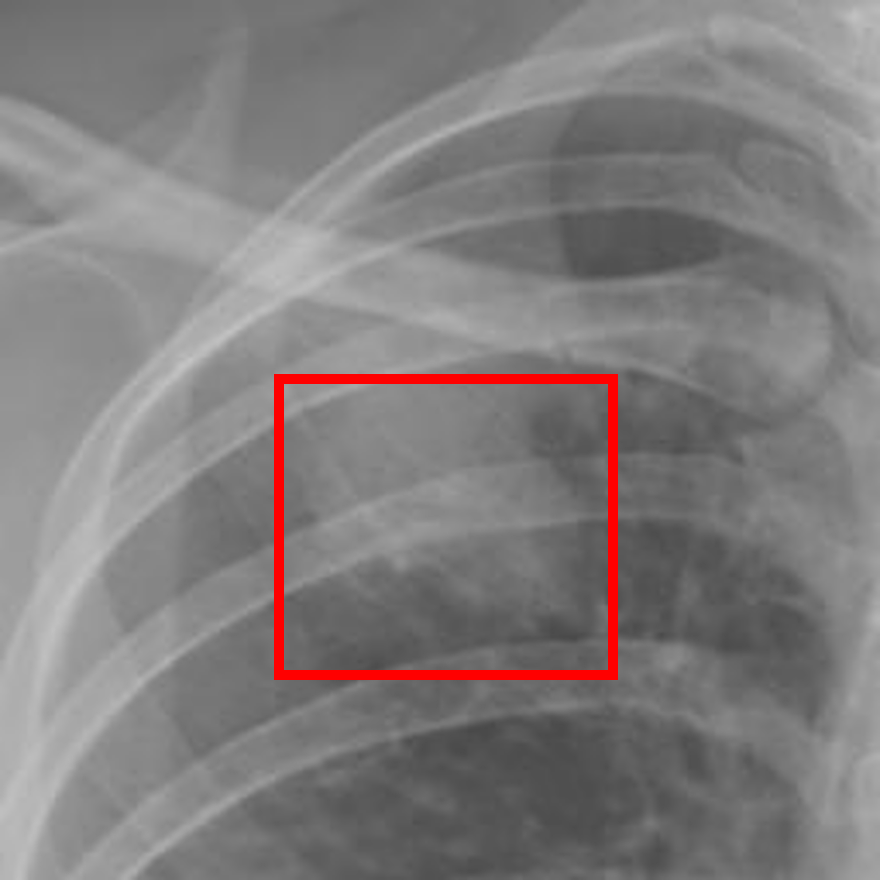

Figure 4 presents a comprehensive visualization of the curriculum learning strategy and its performance impact. Panels (a)–(d) show representative segmentation masks and predictions, highlighting visual improvements. Panels (e)–(h) illustrate synthetic nodules stratified by difficulty, demonstrating the range of training examples used. Finally, panels (i) and (j) provide outcome metrics: the confusion matrix summarizes classification results, and the radar plot compares performance with and without curriculum-based training across key metrics. Together, these results underscore the effectiveness of difficulty-aware augmentation and staged learning.

Refer to caption

(a) Ground Truth 1

(b) Prediction 1

(c) Ground Truth 2

(d) Prediction 2

(e) Easy

(f) Medium

(g) Hard

(h) Very Hard

(i) Confusion Matrix

(j) Radar Plot

Figure 4: Integrated visualization of the curriculum learning strategy and performance evaluation. Top row: Ground truth masks (a, c) and corresponding predictions (b, d) for two representative cases. Middle row: Synthetic nodule examples across four difficulty levels (e–h), used in curriculum-based training. Bottom row: Classification outcomes using the curriculum learning model—(i) confusion matrix and (j) radar plot comparing curriculum vs. non-curriculum performance.